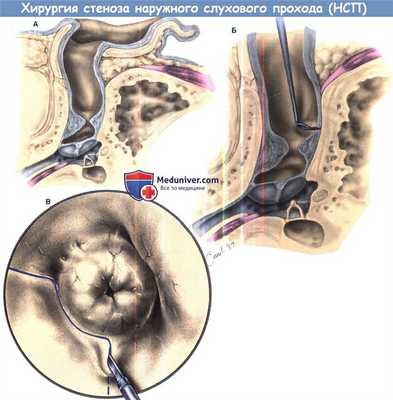

Хирургическое лечение приобретенного стеноза наружного прохода.

(А) Циркулярный фиброзирующий стеноз на уровне кости наружного слухового прохода.

(Б и В) Сосудистая полоска выделяется как можно медиальнее, до безопасного предела.

Лоскут поднимается и ухо смещается кпереди. Затем кожу канала спереди либо надрезают посредине и смещают как «штору» при подъеме в виде имеющего латеральное основание лоскута, либо надрезают с латеральной стороны и удаляют для замены свободным кожным трансплантатом. Рубец часто может быть отсечен от медиального слоя барабанной перепонки, если оставшуюся барабанную перепонку не иссекают. Для выполнения широкой каналопластики применяется сверло.

Для реконструкции берется трансплантат фасции височной мышцы, который используется для восстановления любой перфорации барабанной перепонки с медиальной или латеральной техникой. Спереди кожа канала очищается от повреждений и готовится к пересадке. В идеале, кожа берется дерматомом с внутренней поверхности руки или бедра. Заушной кожи может быть слишком много, но опыт авторов показывает, что полная толщина трансплантата чрезмерна и сжимается до нежелательно небольшого трансплантата, становясь меньше, чем необходимо для охвата кости. Для покрытия кости при недостатке кожи можно использовать и фасцию. Барабанная перепонка может быть покрыта диском Gelfilm. Заушный разрез закрывается и канал заполняется гелевой пеной.

Приживлению трансплантатов и сосудистой полоски во многих случаях способствуют стент или сложенные в виде бутона полоски шелка или силикона.

(Г) Выполнен заушный разрез.

(Д) Сосудистая полоска поднята к верху наружного прохода.

(Е) Во время прохождения в пространство среднего уха массив рубцовой ткани приподнимается от задней стенки слухового прохода. Хирургическое лечение приобретенного стеноза наружного прохода.

(Ж) Иссечение заднего фиброзного стеноза.

(З) Иссечение передних стенозирующих рубцовых тканей, с оставлением спереди остатков барабанной перепонки, если это вообще возможно.

Проход увеличивается сверлами до тех пор, пока сквозь кость не станут видны воздухоносные ячейки.

(И) барабанная перепонка и проход закрывается фасцией и канал наполняется мазью.